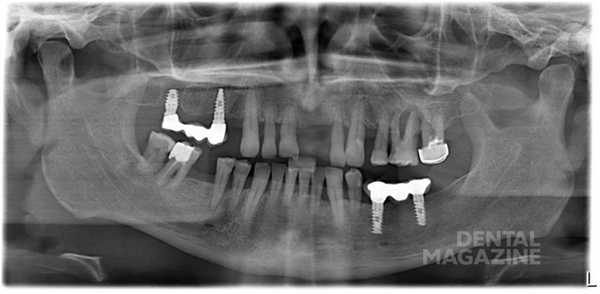

Согласно отчету шестого Европейского семинара по пародонтологии в 2008 году, мукозит и периимплантит признаны инфекционными заболеваниями, вызываемыми бактериями (Cindy& Meyle,2008, Consensus Report EP6). Мукозитом называют воспалительное поражение, которое ограничивается слизистой вокруг имплантата (рис. 1 а, б, в) . Периимплантит — это патологическое состояние, возникающее в тканях, окружающих дентальные имплантаты, вызываемое микроорганизмами и характеризующееся воспалением тканей и потерей кости вокруг имплантата (рис. 2, 3 а, б) .

Рис. 2. Периимплантит. Резорбция кости на 2/3 длины имплантата через 3 года после установки имплантата.

Имплантаты в области 15-го, 17-го зубов установлены 7 лет назад. Пациент игнорировал плановые осмотры, диспансерное наблюдение, периодически появлялся в клинике для удаления зубов, при этом отказываясь от лечения пародонтита. Все отсутствующие зубы удалены по пародонтологическим показаниям. При каждом визите проводилась беседа о рисках потери своих зубов и имплантатов. Пациент с хроническим нелеченым пародонтитом тяжелой степени тяжести обратился в клинику с жалобами на подвижность мостовидного протеза 15-17. Удален мостовидный протез 15-17 вместе с имплантатами в связи с полной дезинтеграцией.